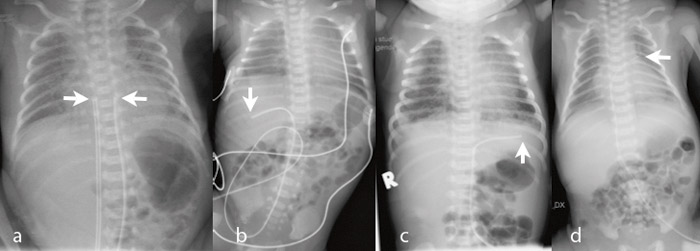

Tabell 1 angir kateterposisjonene. Av navlearteriekatetrene var 45/99 (45 %) primært riktig plassert, og 77/278 (28 %) av venekatetrene. Navlearteriekatetre lå oftere for lavt (44/99; 44 %) enn for høyt (10/99; 10 %) (p < 0,001). Tilsvarende lå flere navlevenekatetre for lavt (126/278; 45 %) enn for høyt (75/278; 27 %) (p < 0,001). Hos 14 (5 %) av venekatetrene og seks (6 %) av arteriekatetrene var det krøll på kateteret (fig 3). For venekatetrene lå krøllen hos 11 i ductus venosus og hos tre i portveneområdet. For arteriekatetrene lå krøllen hos alle i aorta.

Både navlevene- og navlearteriekatetre kan krølles opp hvis spissen fanges av karets intima (fig 3). Økt fare for intimaskade med trombosering kan da foreligge. Krøllen bør rettes ut ved å trekke kateteret tilbake.